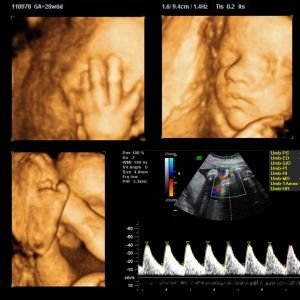

3D, 4D & 5D Ultrasound Imaging

These advanced ultrasound techniques offer enhanced visualization, especially useful for fetal imaging and observing organ development in detail.